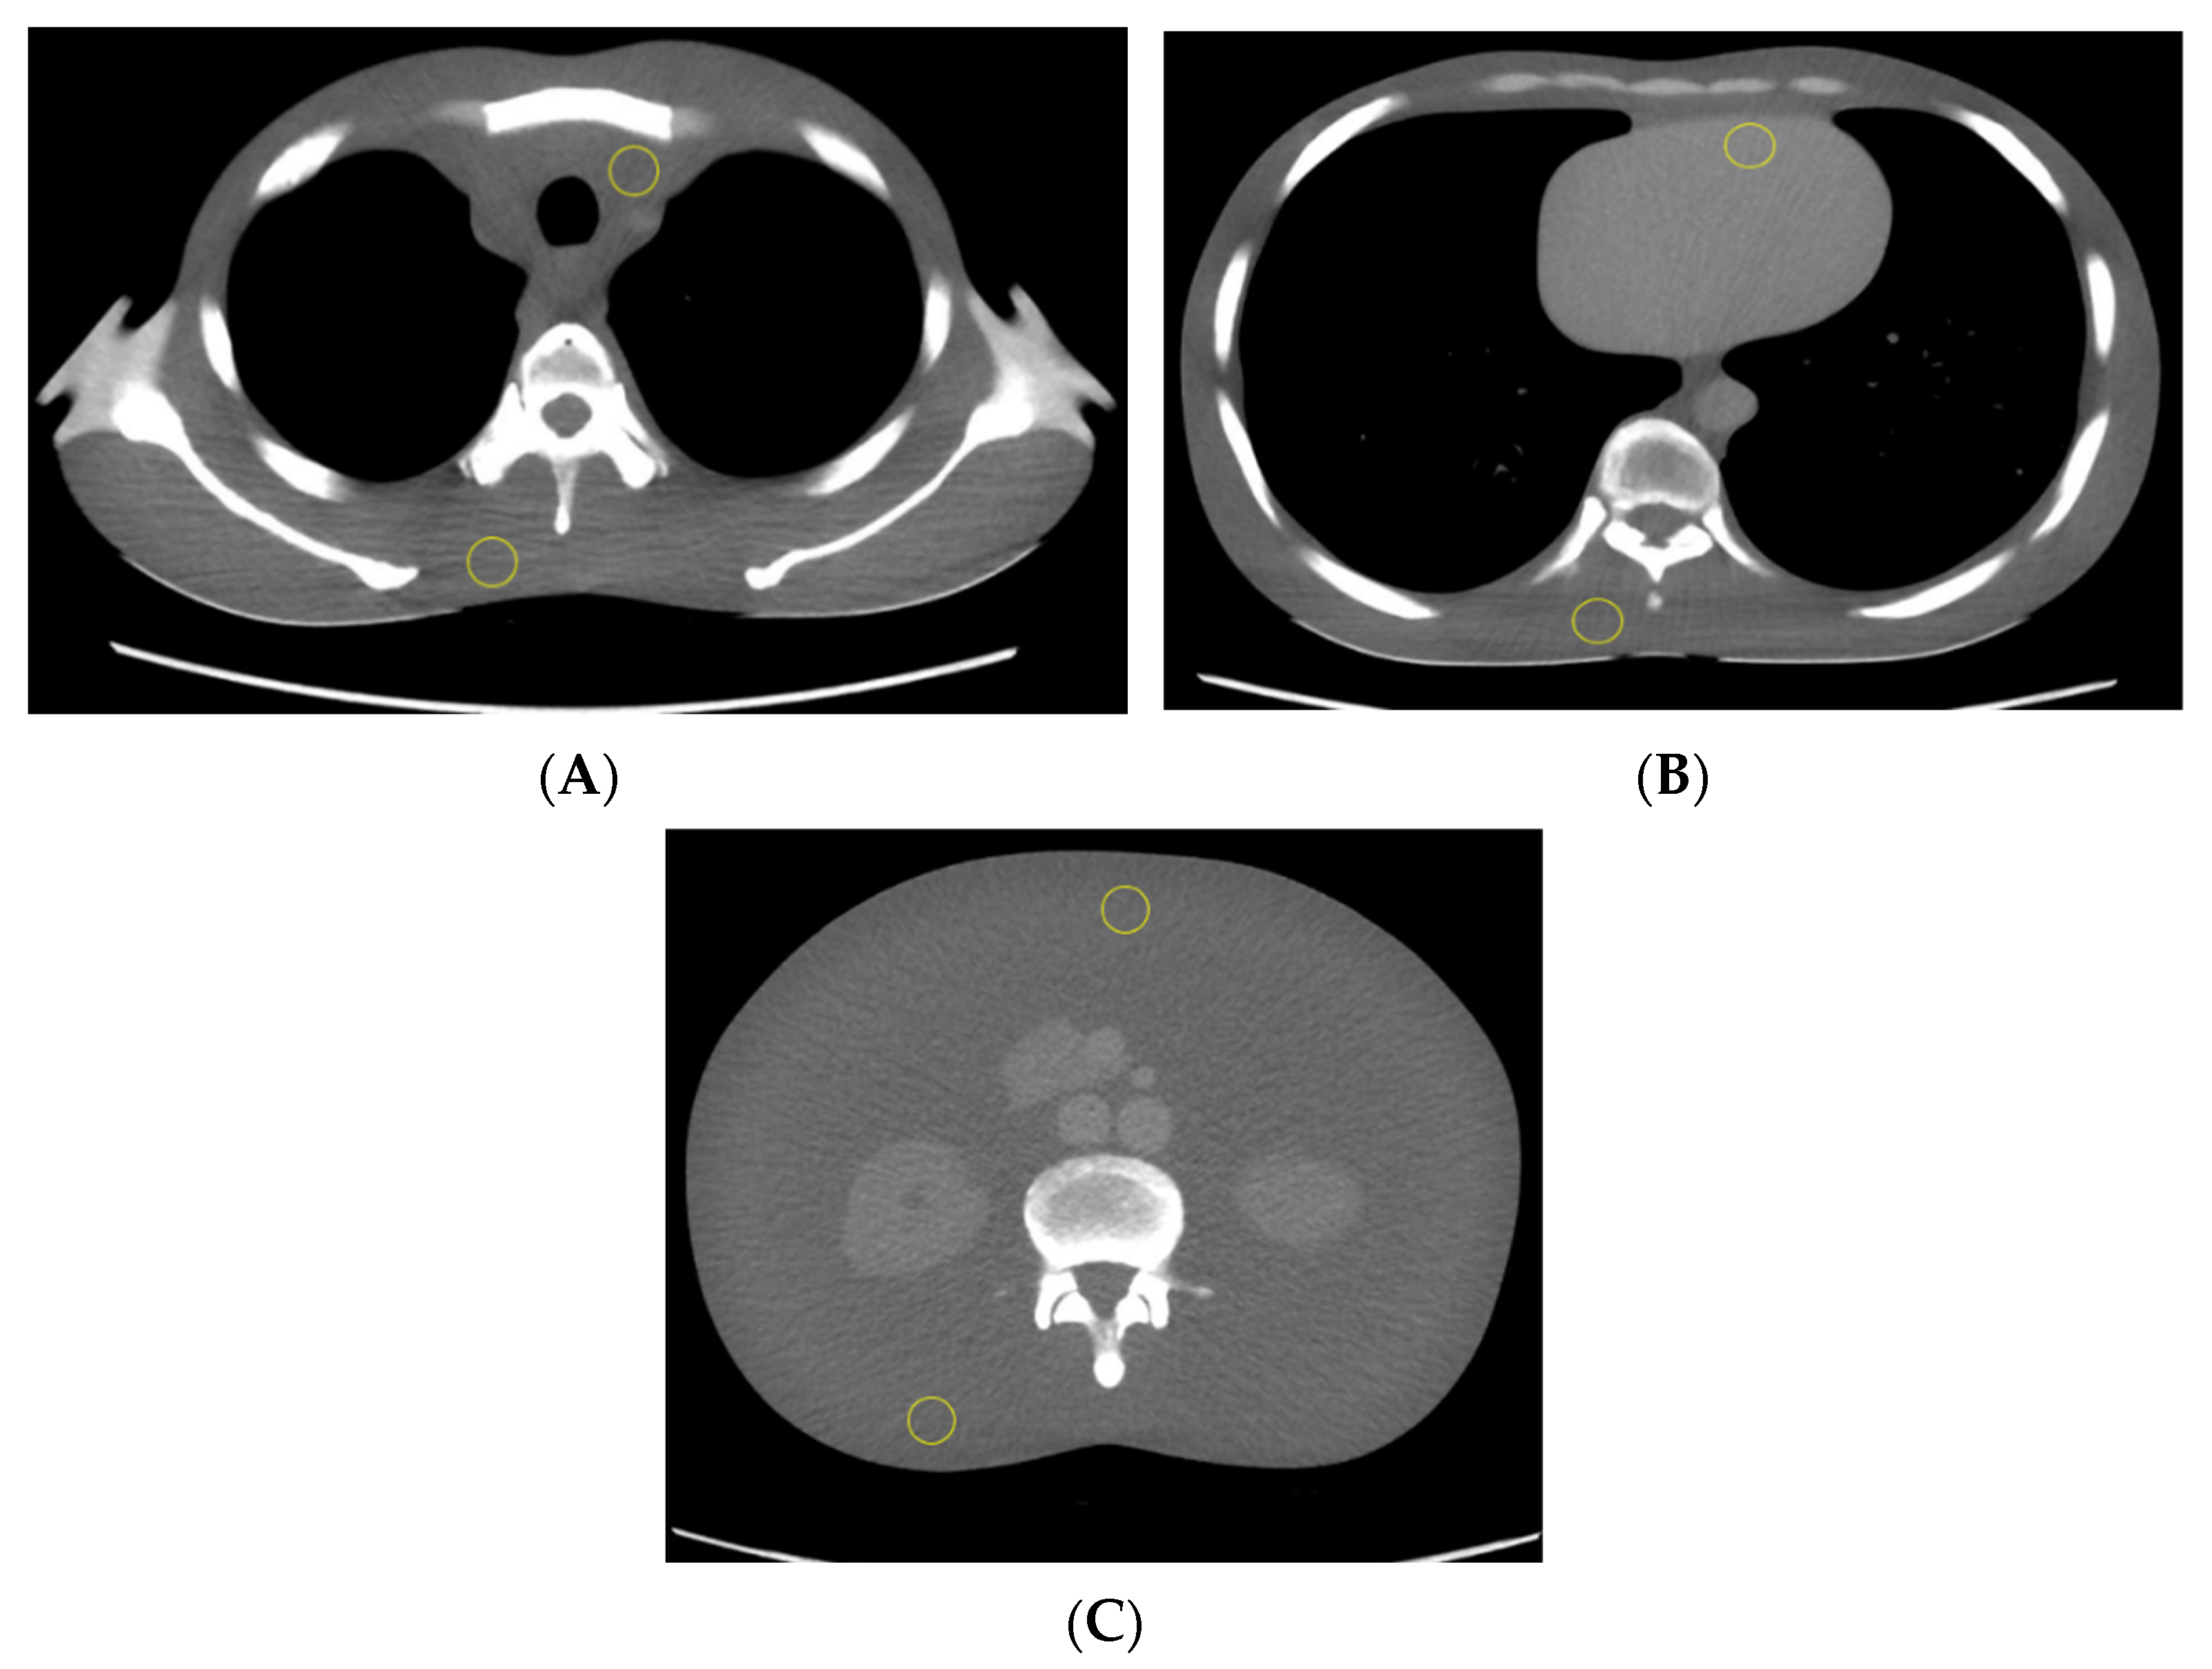

2.1. Phantom and CT Protocol

2.2. CT Number and Dose Measurements